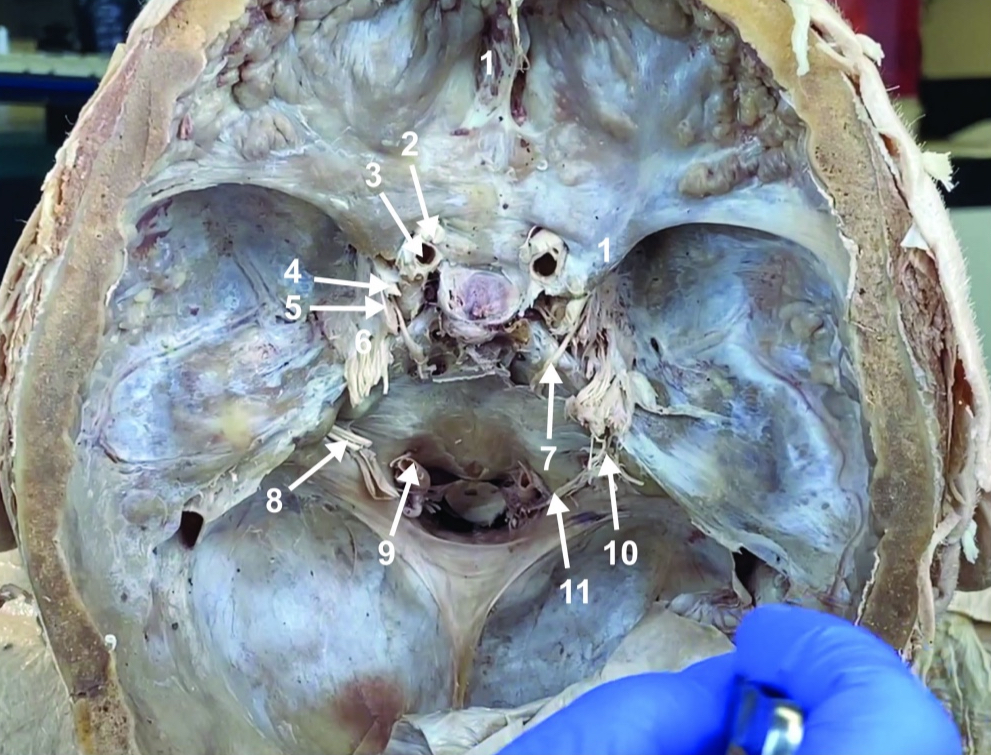

Foramen magnum

ID structure

Foramen ovale

ID structure

Foramen spinosum

ID structure

Cribiform plate

ID structure

Optic n. (CN II)

ID structure

Internal carotid a. (ICA)

ID structure

Occulomotor n. (CN III)

ID structure

Trochlear n. (CN IV)

ID structure

Trigeminal n. (CN V)

ID structure

Abducent n. (CN VI)

ID structure

Facial and vestibulocochlear n. (CN VII and VIII)

ID structure

Vertebral a.

ID structure

Glossopharyngeal and vagus n. (CN IX and X)

ID structure

Root of spinal accessory n. (root of CN XI)

ID structure

Ophthalmic division of CN V (CN V1)

ID structure

Maxillary division of CN V (CN V2)

ID structure

Mandibular division of CN V (CN V3)

ID structure

Foramen rotundum

ID structure

Foramen ovale

ID structure

Trochlear n. (CN IV)

ID structure

Abducent n. (CN VI)

ID structure